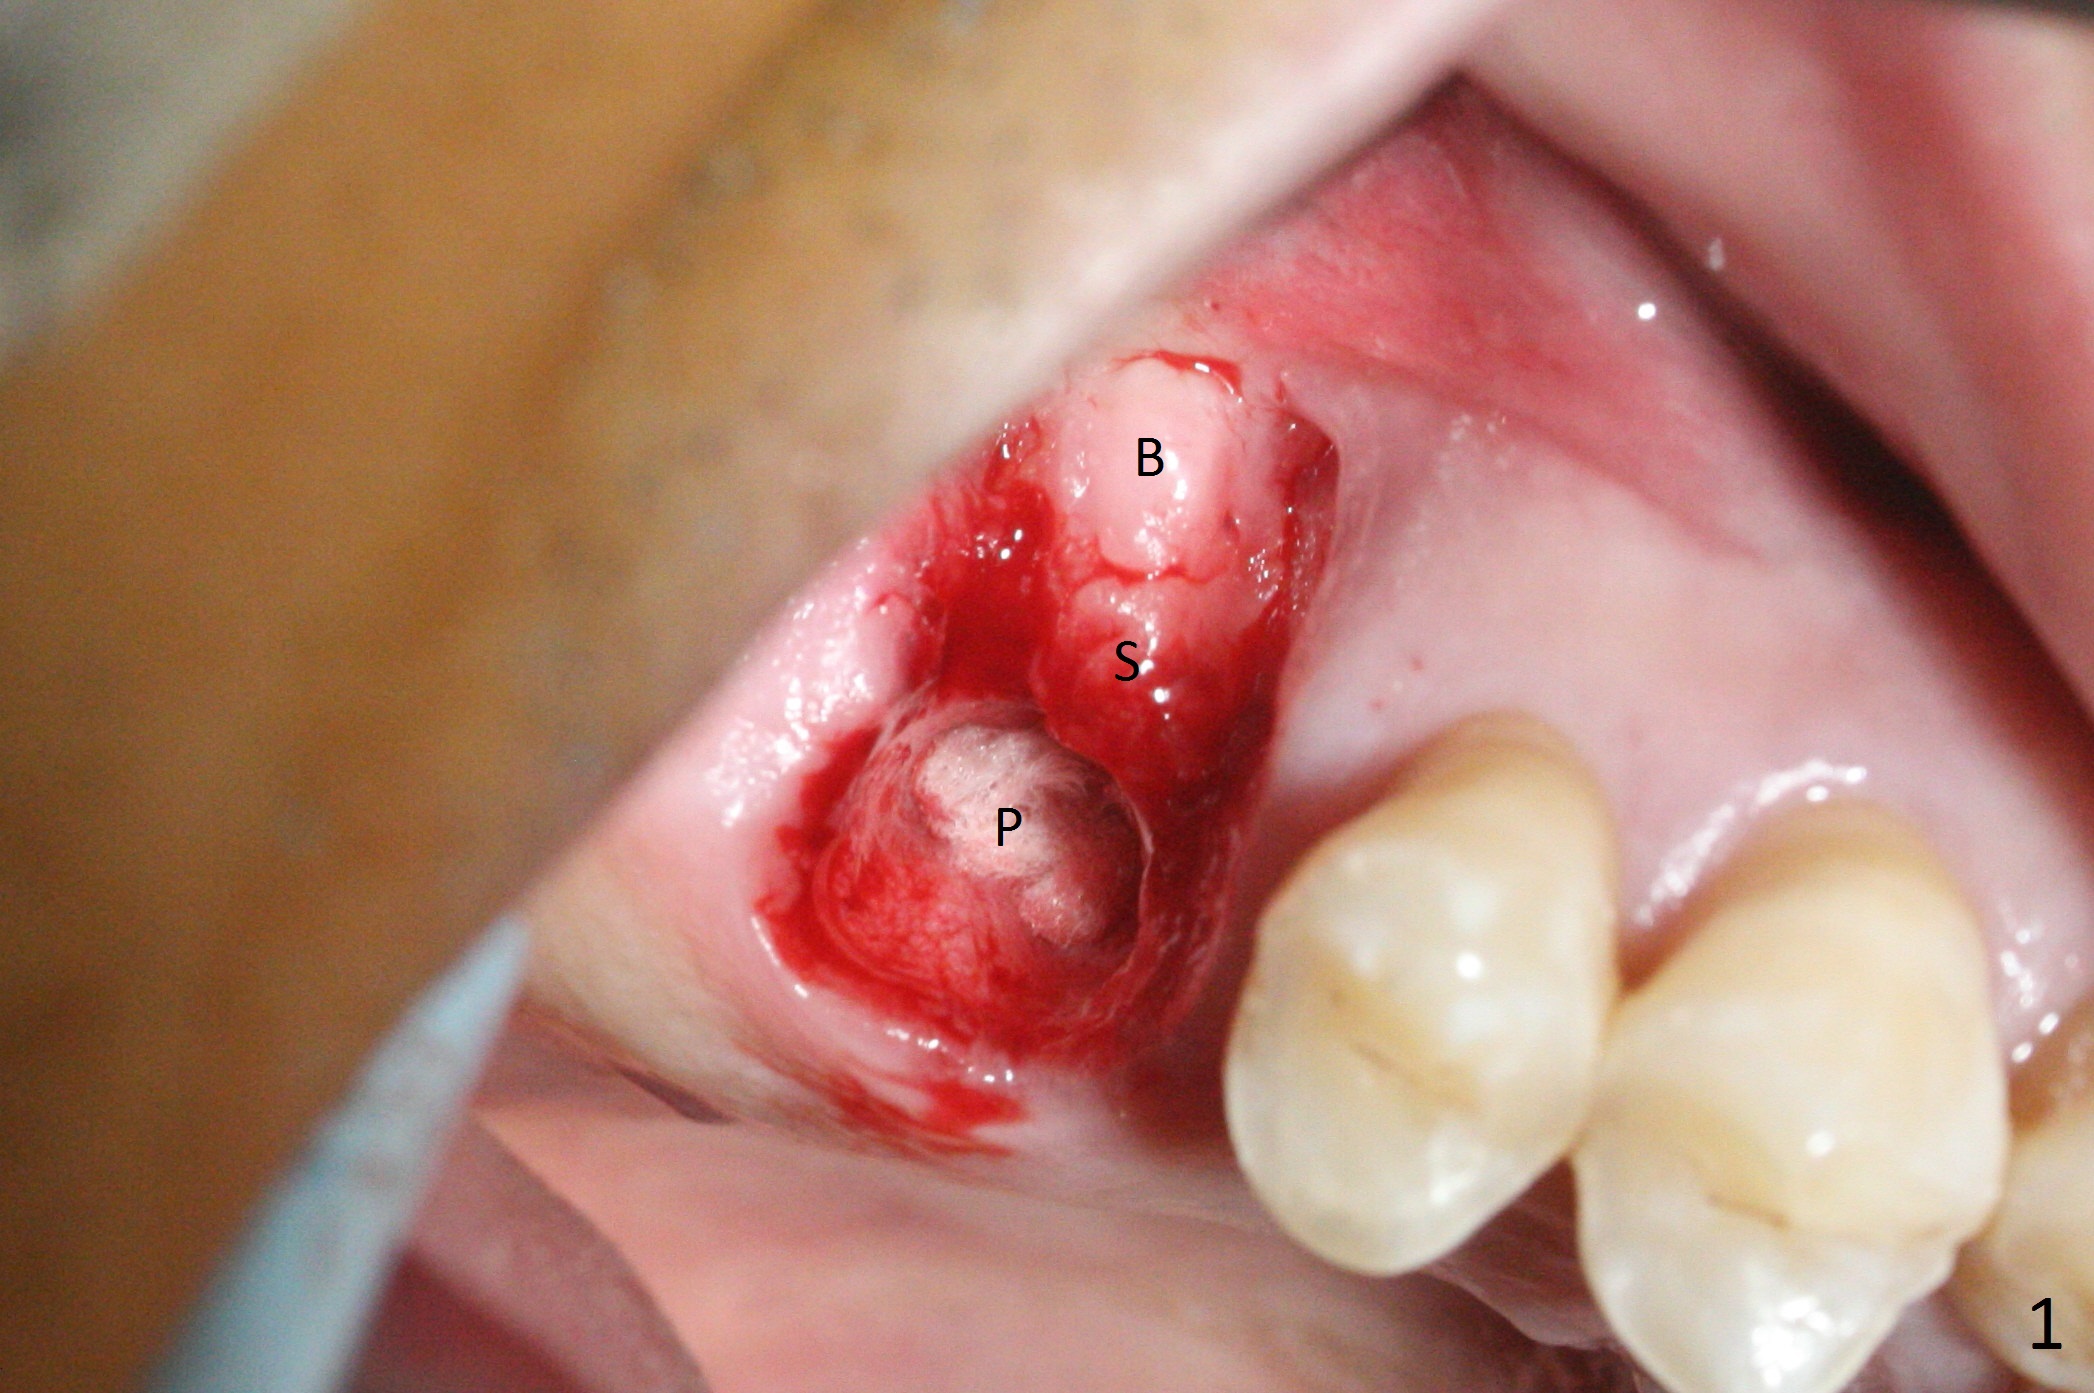

The palatal socket (Fig.1 P, packed with gauze) is intact, but implant trajectory may not be ideal. Buccal to the palatal socket are 2 pieces of the gingiva, buccal (B) and Septal (S). After the septal gingiva is pushed buccally (Fig.2 arrow), the underlying sloped septal bone is exposed (Fig.3 white area). Osteotomy is established as palatal as possible (Fig3 black circle) using DIO Sinus Master Kit, supplemented by Tatum osteotomes and DIO SM 3.8 mm tap drill for final sinus lift (Fig.4). Following further osteotomy using 4.1 and 4.5 mm taps, a 4.5x10 mm implant (Fig.6,7) with insertion torque >65 Ncm. Due to buccal bone loss, the coronal buccal threads are exposed 1-2 mm, which is covered by combination of allograft, autogenous bone and Osteogen. Prior to implantation, PRF plug and bone graft are used for sinus lift. The septal gingiva now is approximately 1-2 mm coronal to the implant plateau (Fig.5 S). The most coronal buccal gingival defect is covered by 3 pieces of PRF membrane (Fig.5 M) against a 6.8x5.5(6) mm abutment (A). Finally the socket is protected by periodontal dressing (Fig.8).